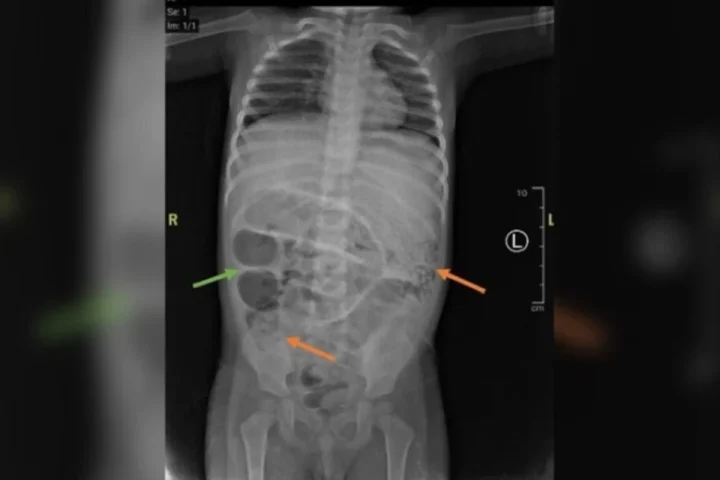

Criança passa por cirurgia após vomitar vermes; ele foi diagnosticado com obstrução intestinal